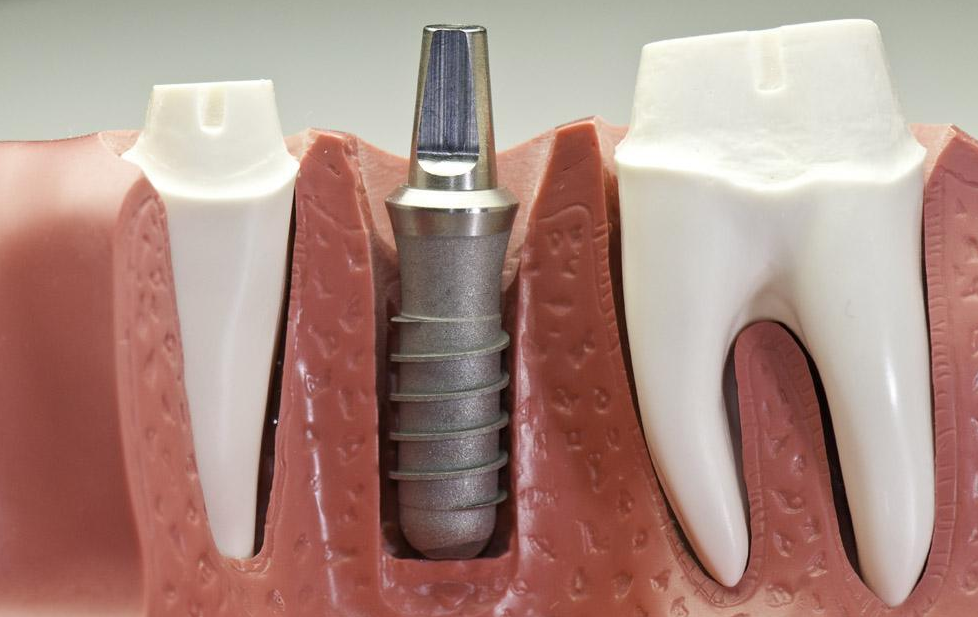

牙齿缺失现在有很多人选择种植牙,现在听说即刻种植牙要比种植牙好,很多人对其并不是很了解,所以想询问一下:廊坊即刻种植的优点有哪些呢?

廊坊圣洁口腔医院专家指出:即刻种植牙和普通的种植牙效果是一样的,即刻种植牙的优点,主要体现在以下几方面:

第一、缩短了时间:即刻种植牙拔掉牙齿后不需要等待太长的时间,我们可以立刻植入种植体,这样可以早期恢复咀嚼功能,可以很大程度的缩短治疗时间。 》》》相关阅读:牙齿掉了,不补有什么危害?

第二、避免牙龈萎缩:普通的拔牙后要等待1—3个月伤口与牙槽骨愈合之后,一些人可能牙槽骨愈合之后没有发现,这样是很容易导致牙龈萎缩的,而即刻种植牙拔掉牙齿后就可以立刻做种植牙,是完全可以避免这个问题的。

第三、可以植入理想的位置:即刻种植牙可以植入牙根的时候可以参照原有的牙根的方向,可以直接植入到理想的位置,这样是可靠的,而且美观自然。